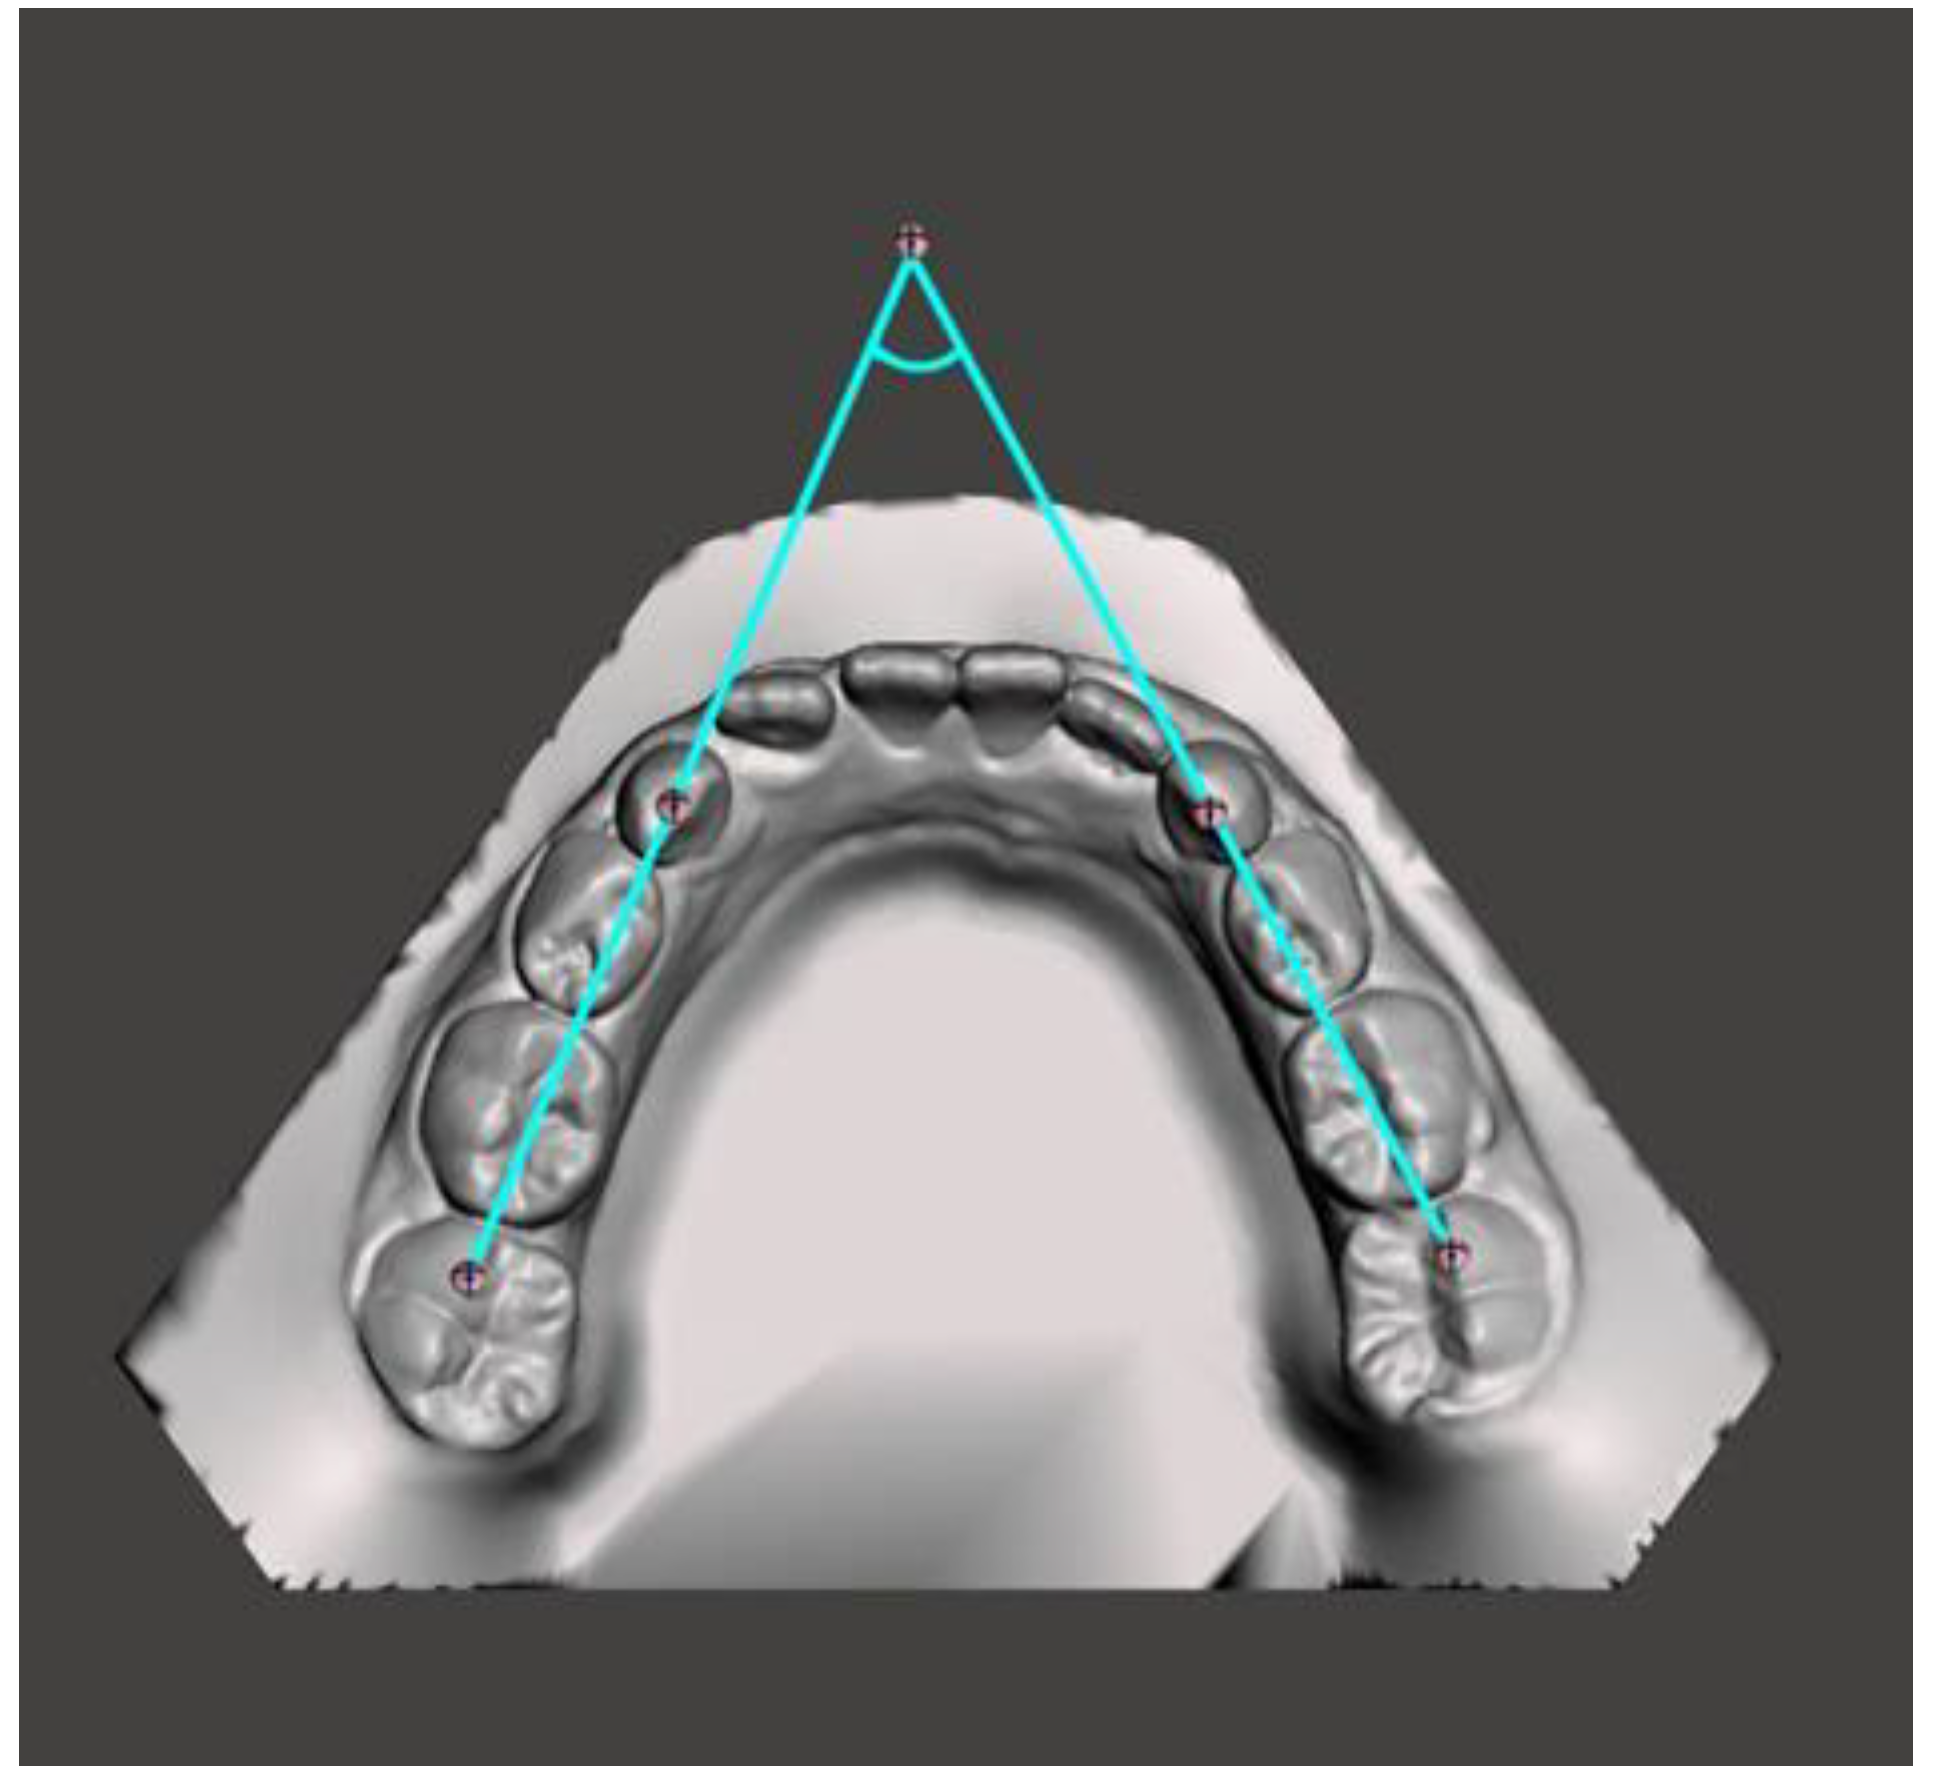

Intermolar angle.

Figure 6.